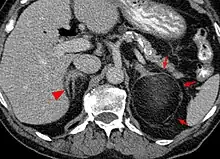

Most myelolipomas are unexpected findings on CT scans and MRI scans of the abdomen. They may sometimes be seen on a plain X-ray films.[4]